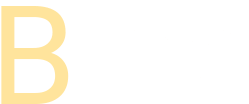

今回は小児の反対咬合の症例です。初診で来院されるほとんどの方は治療開始のタイミングでお悩みになっているのではないでしょうか。

反対咬合は前歯の被さりが反対であるだけではなく、遺伝性の骨格的な反対咬合の場合が多いですのでまずは早めに相談にいらしていただければと思います。

前歯の被さりが反対のままですと上アゴの前方への成長が抑制されてしまいますし、前歯のみの部分的な反対咬合から骨格的な反対咬合に移行してしまう可能性もあります。

反対咬合は前歯だけでなく側方歯の被さりも側方拡大するなどで早期に改善しておくことが重要です。

前歯の歯並びと被さりが改善されたらこれでおしまい・・ではなくてここからが本当のスタートです。本症例ではこれから側方歯が乳歯から永久歯へと交換が始まります。